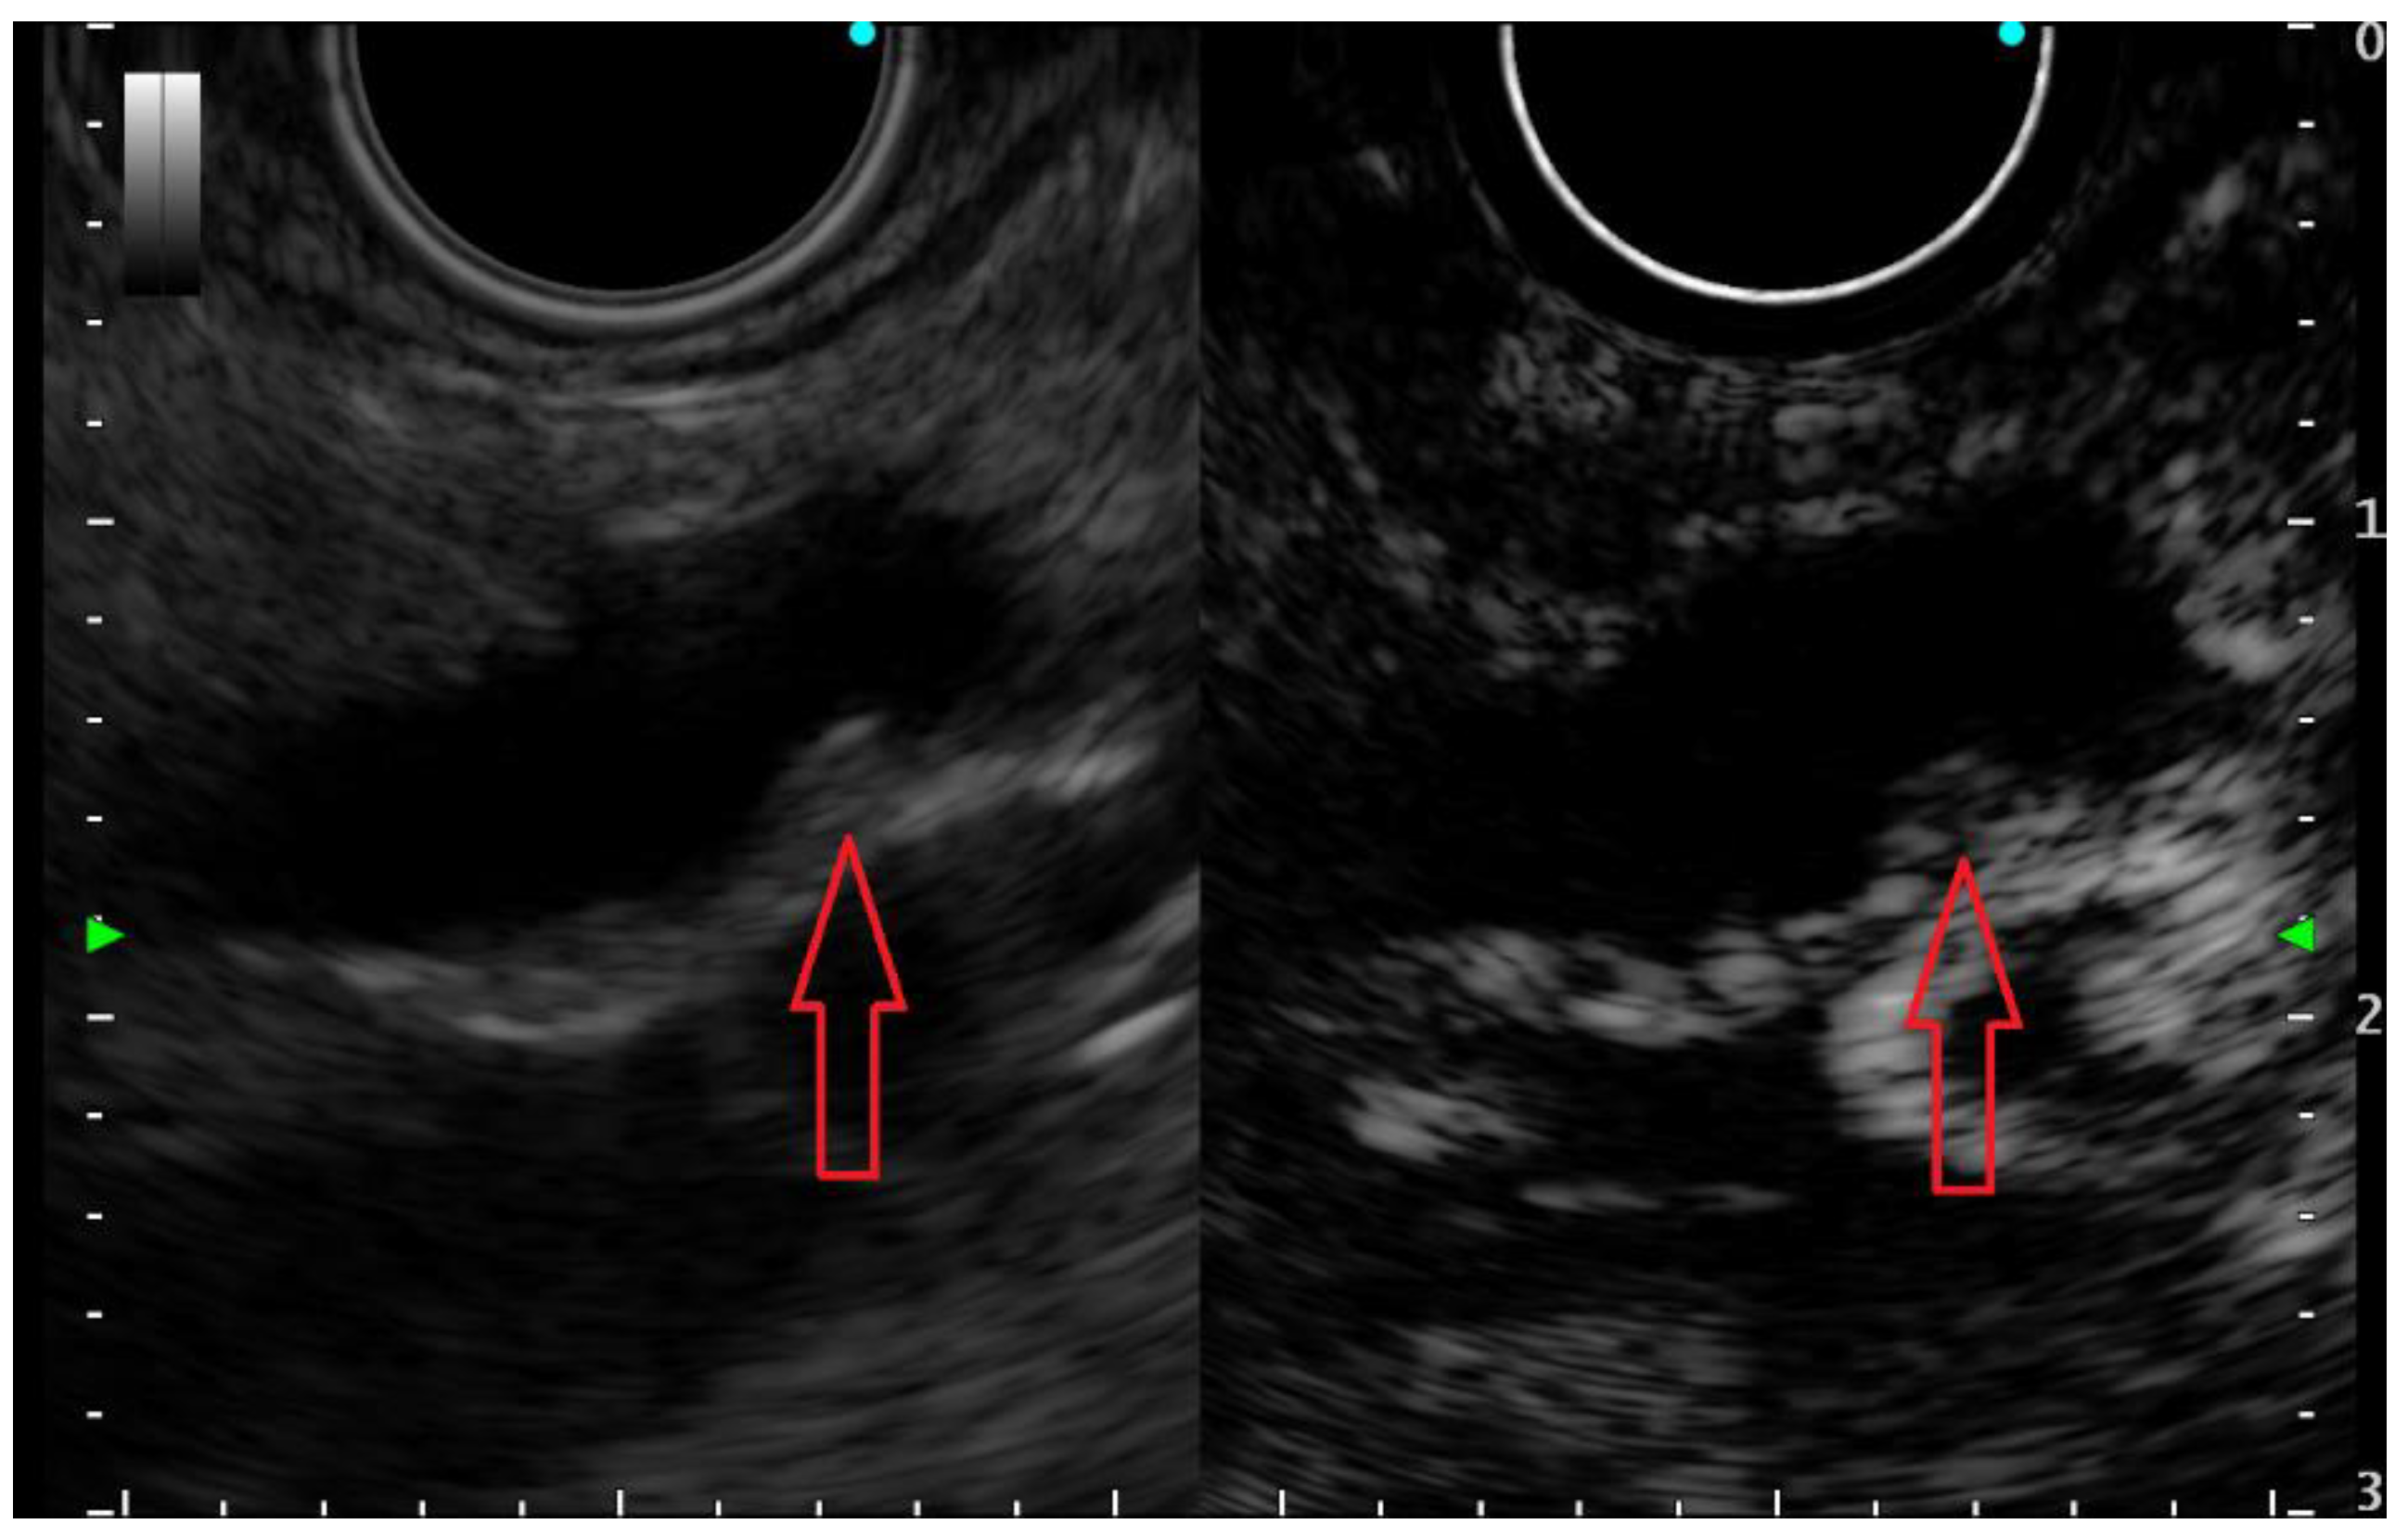

- Fusaroli, P.; Serrani, M.; De Giorgio, R.; D’Ercole, M.C.; Ceroni, L.; Lisotti, A.; Caletti, G. Contrast harmonicendoscopic ultrasound is useful to identify neoplastic features of pancreatic cysts (with videos). Pancreas 2016, 45, 265–268. [Google Scholar] [CrossRef]

- Yamashita, Y.; Ueda, K.; Itonaga, M.; Yoshida, T.; Maeda, H.; Maekita, T.; Iguch, M.; Tamai, H.; Ichinose, M.; Kato, J. Usefulness of contrastenhanced endoscopic sonography for discriminating mural nodules from mucous clots in intraductal papillary mucinous neoplasms: A single-center prospective study. J. Ultrasound Med. 2013, 32, 61–68. [Google Scholar] [CrossRef]